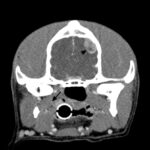

Approximately one month later, the dog was returned by the owners to CUVS for computerized tomographic analysis. The analysis revealed a large mass located in the deep tissues of the upper cervical region, which was suspected to be associated with the carotid artery or body or both (Figure 3a-b). The appearance of the thyroid glands was unremarkable. Small brain lesions (Figure 3a) and pulmonary nodules were also noted. Splenic nodules were still present (Figure 3c).